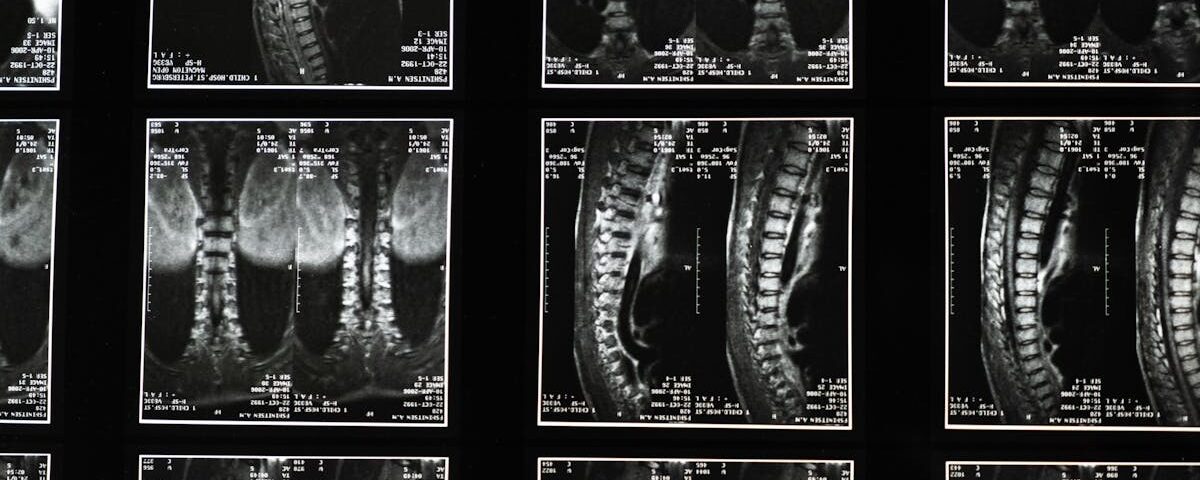

Quels examens permettent de diagnostiquer un pincement discal?

Une IRM ou une radiographie est souvent utilisée pour confirmer le diagnostic d’un pincement discal ou d’un disque écrasé.